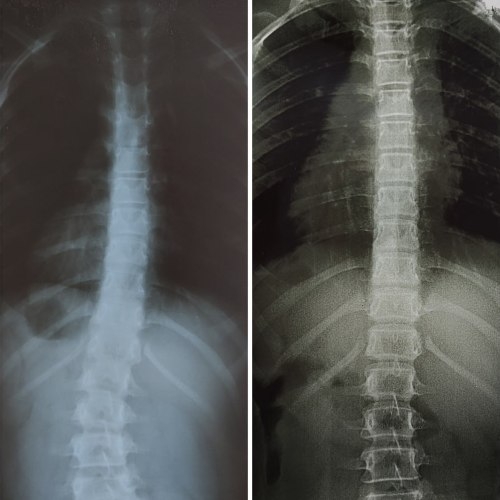

Чем дальше, тем сильнее перенапрягаются мышцы. Смещаются позвонки. Если вопрос не решать, то боль становится хронической. Могут развиваться осложнения — искривление позвоночника, смещение позвонков, протрузии и грыжи.

Чтобы вы тоже смогли получить

вот такие результаты: